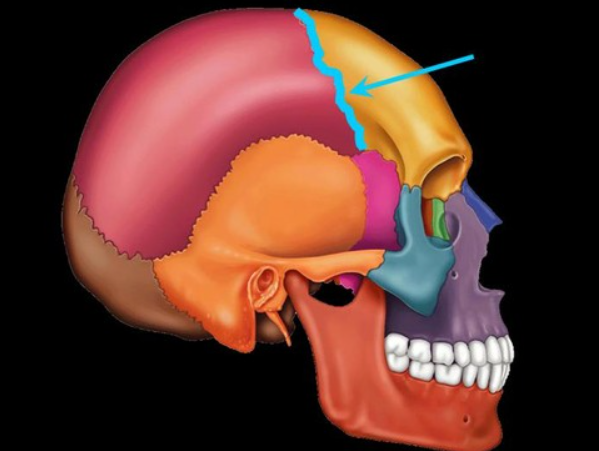

coronal suture

sits between the frontal lobe and parietal lobe